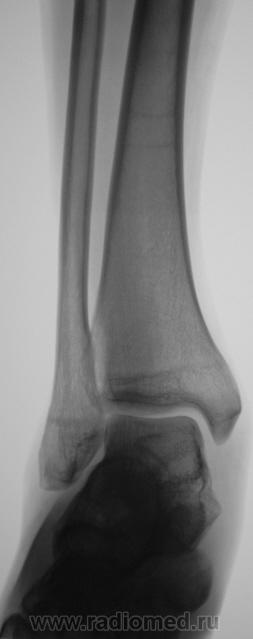

Пол пациента: Мужской пол Тип патологии: Другое Область исследования: Скелетно-мышечная система Методы исследования: Rg Пациент направлен врачом хирургом в рентгеновский кабинет по поводу болей в голеностопном суставе. Произведена рентгенография голеностопного сустава Ваше мнение уважаемые коллеги? Tue, 06/10/2009 - 22:21 #1 Ермолаев Offline Last seen: 8 years 11 months ago Joined: 07.02.2009 - 16:33 Posts: 670 Думаю, что имеет место артроз голеностопного сустава и таранно-ладьевидного, таранно-пяточного суставов. Только это следствие, а причина мне видится в наличии повреждения дистального межберцового синдесмоза. dok Tue, 06/10/2009 - 22:48 #2 В.Б. Серов Offline Last seen: 1 month 2 weeks ago Joined: 16.07.2008 - 10:15 Posts: 1361 Дугообразная деформация костей, с линейными зонами перестройки, плоскостопие. Полный комплект дефектов Зри в корень!

Думаю, что имеет место артроз голеностопного сустава и таранно-ладьевидного, таранно-пяточного суставов. Только это следствие, а причина мне видится в наличии повреждения дистального межберцового синдесмоза.

Дугообразная деформация костей, с линейными зонами перестройки, плоскостопие. Полный комплект дефектов